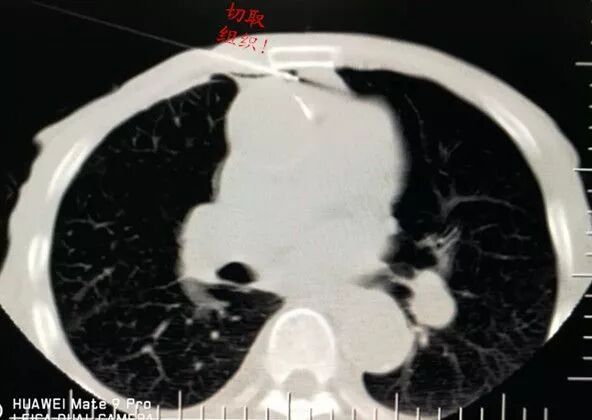

選擇右成角入路,穿越胸骨與主動脈間隙,該間隙僅僅10mm,并避開右胸廓內動脈,精細操作,先置入導針

再置入16G切割活檢槍,稍有偏差便可導致升主動脈損傷破裂,導致災難性后果發(fā)生。

順利規(guī)避大血管進入靶病灶,激發(fā)活檢槍后完成病變組織切割取材。